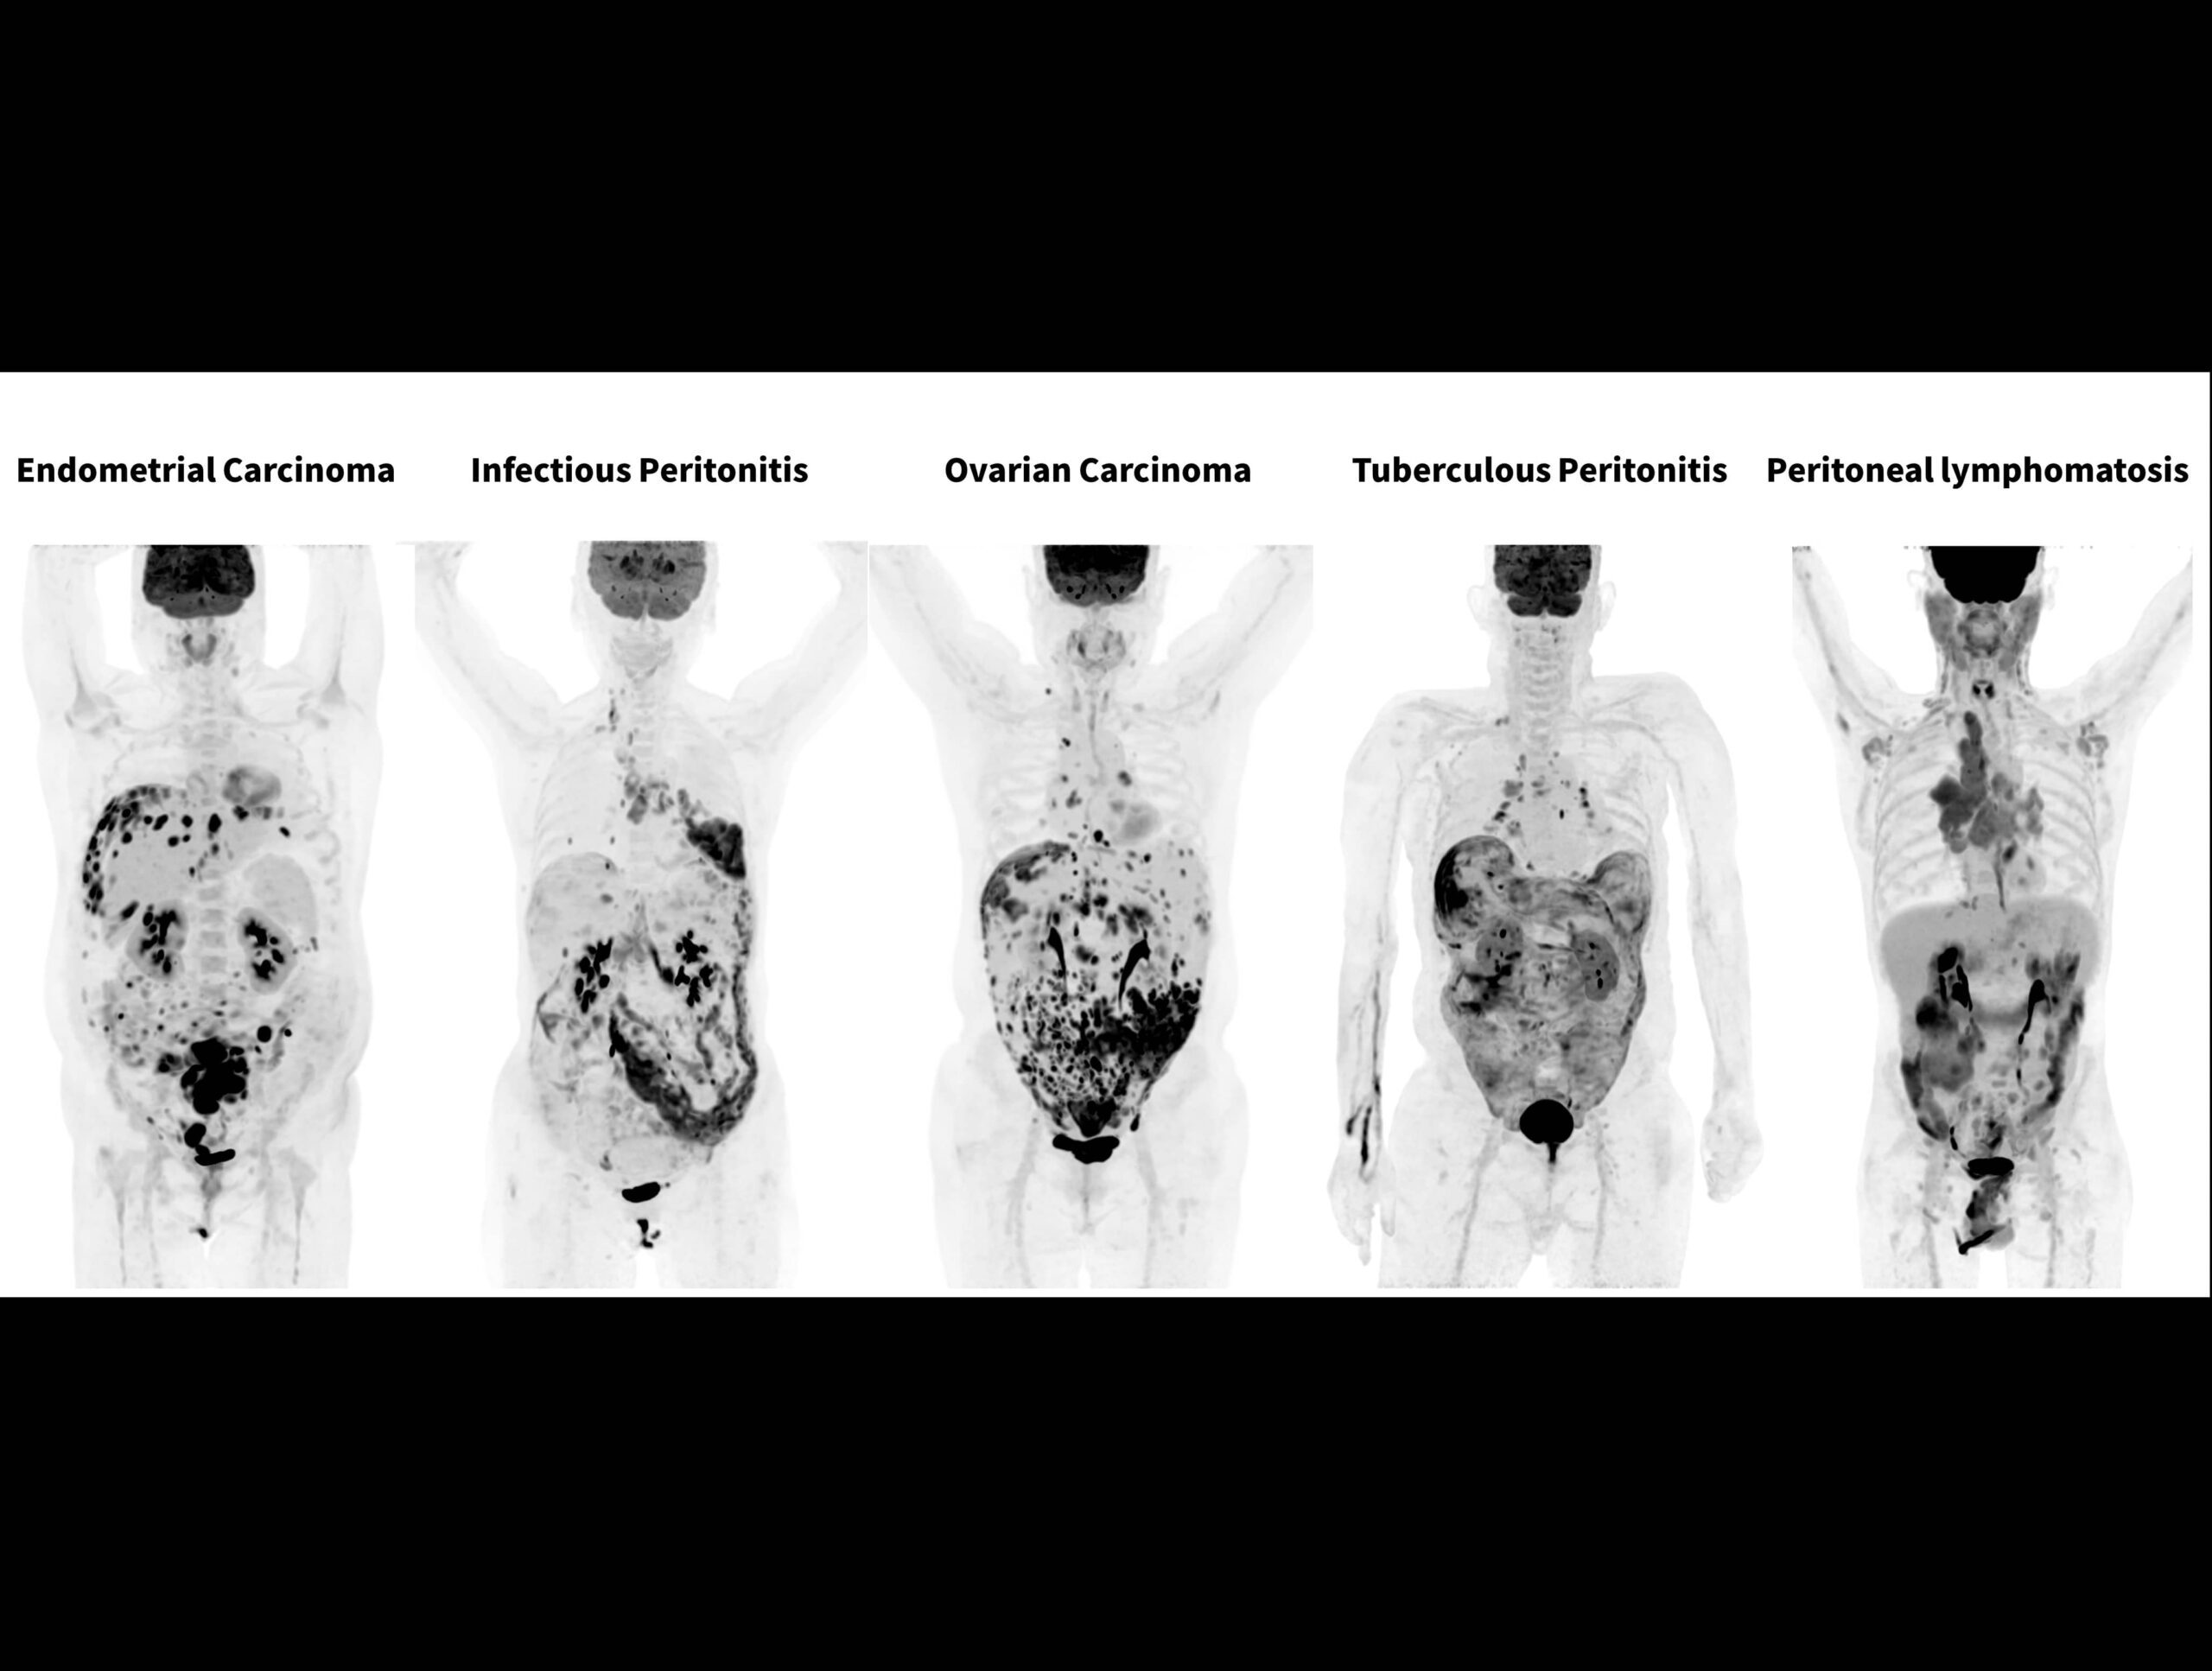

Sistemul high-resolution cu performanță TOF de 189 ps oferă imagini excepționale pentru afecțiuni peritoneale și omentale